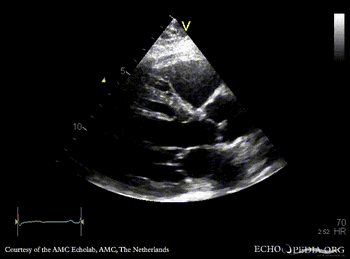

Quadricuspid aortic valve

Courtesy of: AMC Echolab, AMC, The Netherlands

PLAX: dilated left ventricle and aortic root in patient with quadricuspid aortic valve PSAX: quadricuspid aortic valve